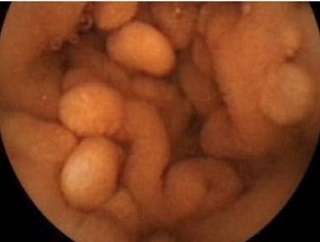

ポイツ・ジェガーズ症候群(Peutz-Jeghers症候群)は、常染色体性優性遺伝による癌抑制遺伝子Liver Kinase B1 (LKB1 or STK11)の機能喪失型変異が原因です。

- 小腸ポリポーシス(過誤腫ポリープ);1~3cmのポリープが小腸(特に空腸)に多発。有茎性・分葉状が多く、高頻度に再燃性腸閉塞・腸重積。慢性的な腸出血(下血)

- 悪性腫瘍の合併(50歳までに30%、70歳までに80%)

消化器癌が最多(60%);食道、胃、小腸、大腸、膵臓